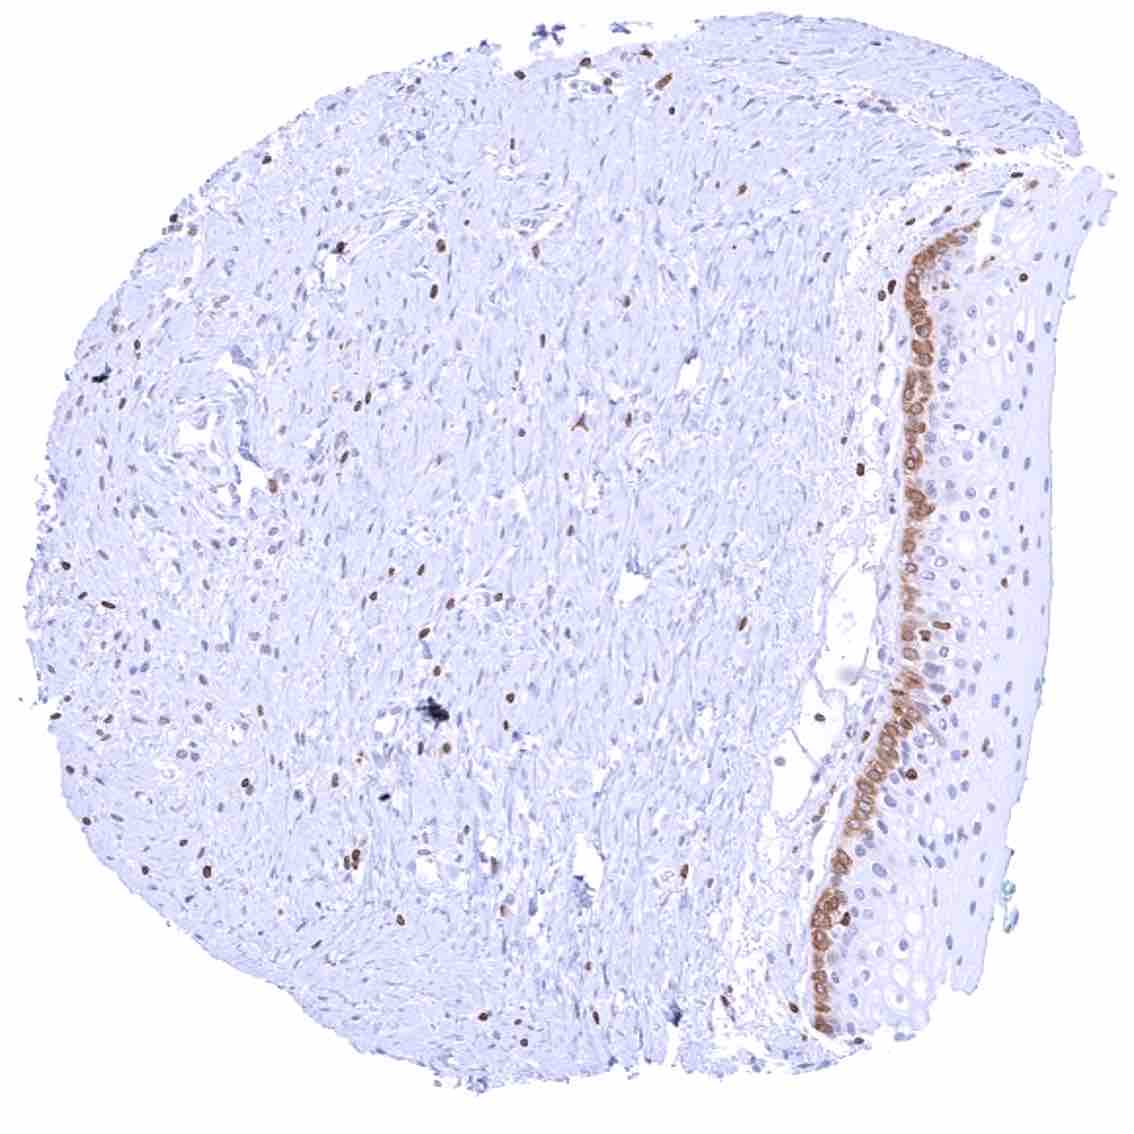

Comparison of antibodies: True expression of bcl-2 in all cell types with documented bcl-2 immunostaining by MSVA-402M is validated by identical staining patterns obtained by a second, independent commercially available bcl-2 antibody, termed “validation antibody” for all analyzed tissues.